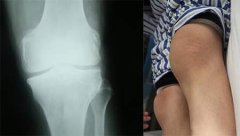

• 膝关节疼痛不在意 转化成风湿性关节炎才着急

患者早年出现典型风湿性关节炎症状,膝关节疼痛、肿胀,未予重视 ...